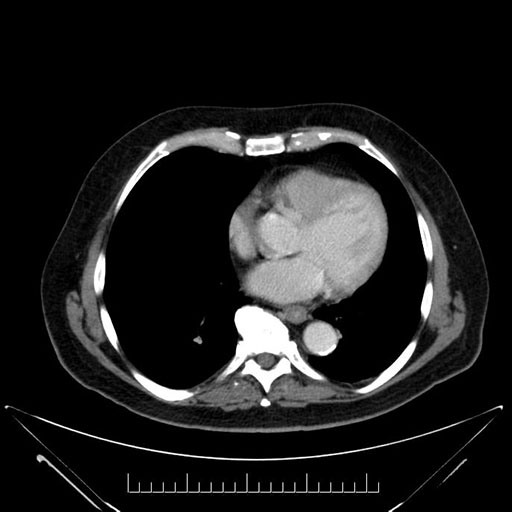

Imaging Analysis

Look through the patient's CT scan to identify any areas of concern for the necessary procedure.

Based on your CT findings, which issue(s) would give reason for "planned slowing down moment(s)" in this case?

Considering a standard Whipple procedure, what step(s) of the operation would you do differently in this case?